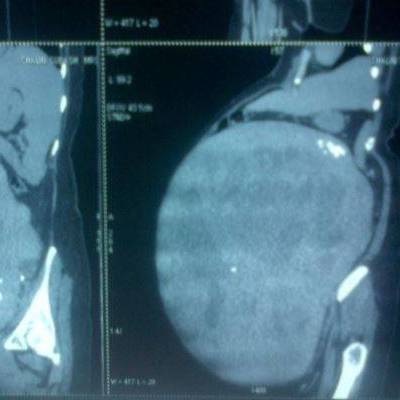

Tumor pesa 13 kg e possui 53 cm de diâmetro | Foto: Reprodução

Cirurgi?es operaram mulher de 52 anos por mais de tr?s horas. A paciente n?o tinha ideia de que havia um tumor gigante instalado no seu ventre. Ele foi considerado o maior tumor uterino do mundo, pesando 13 kg e medindo 53 cent?metros de di?metro.

Quando Latha chegou ao hospital sangrando muito, os m?dicos realizaram uma s?rie de testes. Eles descobriram que ela estava gravemente an?mica, antes de detectar o crescimento do grande mioma ligado ? superf?cie externa do ?tero, que estava pondo press?o sobre o seu corpo e causando os sintomas.

Dr. Mani Mekalai, chefe do departamento do hospital de obstetr?cia e ginecologia, disse que a equipe estava "chocada" ao ver as imagens. "Pelo seu tamanho, o tumor poderia facilmente ter come?ado a crescer h? mais de 20 anos", afirma o m?dico. Latha foi levada para a sala de opera?es dois dias depois de ter sido internada.